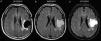

ResultsA total of 107 patients were included, of whom 90 had high-grade gliomas. Inter-rater agreement was excellent, and intra-rater complete (k=0.94 and 1, p<.001). Hyperintense fluid in the resection cavity occurred more commonly (58.9% versus 29.4%, p=.025) and earlier (mean 4.5 versus 9.9 months, p<.001) in high-grade than in low-grade gliomas. Hyperintense fluid was associated with progression in high-grade gliomas, with a sensitivity of 65.7% (95%CI, 54.3–75.6%) and a specificity of 70.6% (95%CI, 46.6–87%), and in low-grade gliomas with a sensitivity of 50% (95%CI, 18.7–81.2%), and a specificity of 81.8% (95%CI, 51.1–96%). The positive predictive value of this sign was 90.6% (95%CI, 79.3–96.3%) for high-grade gliomas, and was higher for grade IV (93.2%, 95%CI, 87.3–99.1%) and lower for grade III (77.8%, 95%CI, 59.6–96%), and low-grade gliomas (60%, 95%CI, 22.9–88.4%). False-positives were identified in 7 patients, due to bleeding or infection. Hyperintense fluid in high-grade gliomas preceded progression in 22 patients (30.1%), with a mean of 4.1 months (SD 2.1, 95% CI, 3.2–5), and associated with poorer progression-free survival (mean 6.8 versus 11.7 months, p=.004).

ConclusionsHyperintense fluid in the resection cavity on follow-up FLAIR sequences occurs more frequently and earlier in high-grade gliomas, and is associated with poorer progression-free survival. Hyperintense fluid is associated with disease progression, and can predict the progression of resected gliomas. False-positives due to bleeding and infection can be observed, and are easily recognizable.